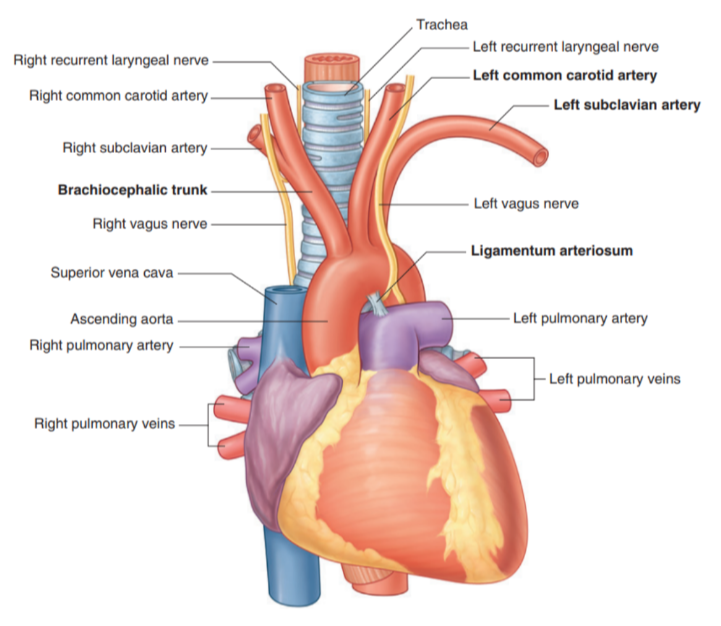

Arch of aorta

The thoracic portion of the aorta can be divided into the ascending aorta, arch of the aorta, & thoracic (descending) aorta —

Only the arch of the aorta is in the superior mediastinum

The arch extends as high as the midlevel of the sternal manubrium & is initially anterior, but later moves laterally to the trachea

From the arch we have 3 branches, each of which is crossed by the left brachiocephalic vein —

Brachiocephalic trunk

Left common carotid artery

Left subclavian artery

In this region we can also recognize the ligamentum arteriosus which is formed from the embryological structure known as the ductus arteriosus.

Branches of arch of aorta

Brachiocephalic trunk —

Largest of the three branches

Originates from behind the manubrium — slightly more anterior than the other branches

At the upper edge of the right sternoclavicular joint divides into —

Right common carotid — supplies right side of head

Right subclavian artery — supplies right upper limb

In some cases may have another branch for the supply of the thymus

Thyroid Ima Artery

Left common carotid artery:

Arises from the arch immediately to the left and slightly posterior to the brachiocephalic trunk

Ascends through the superior mediastinum along the left side of the trachea

Supplies the left side of the head and neck.

Left subclavian artery:

Arises from the arch of the aorta immediately to the left of, and slightly posterior to the left common carotid artery

Ascends through the superior mediastinum along the left side of the trachea

The major blood supply to the left upper limb.